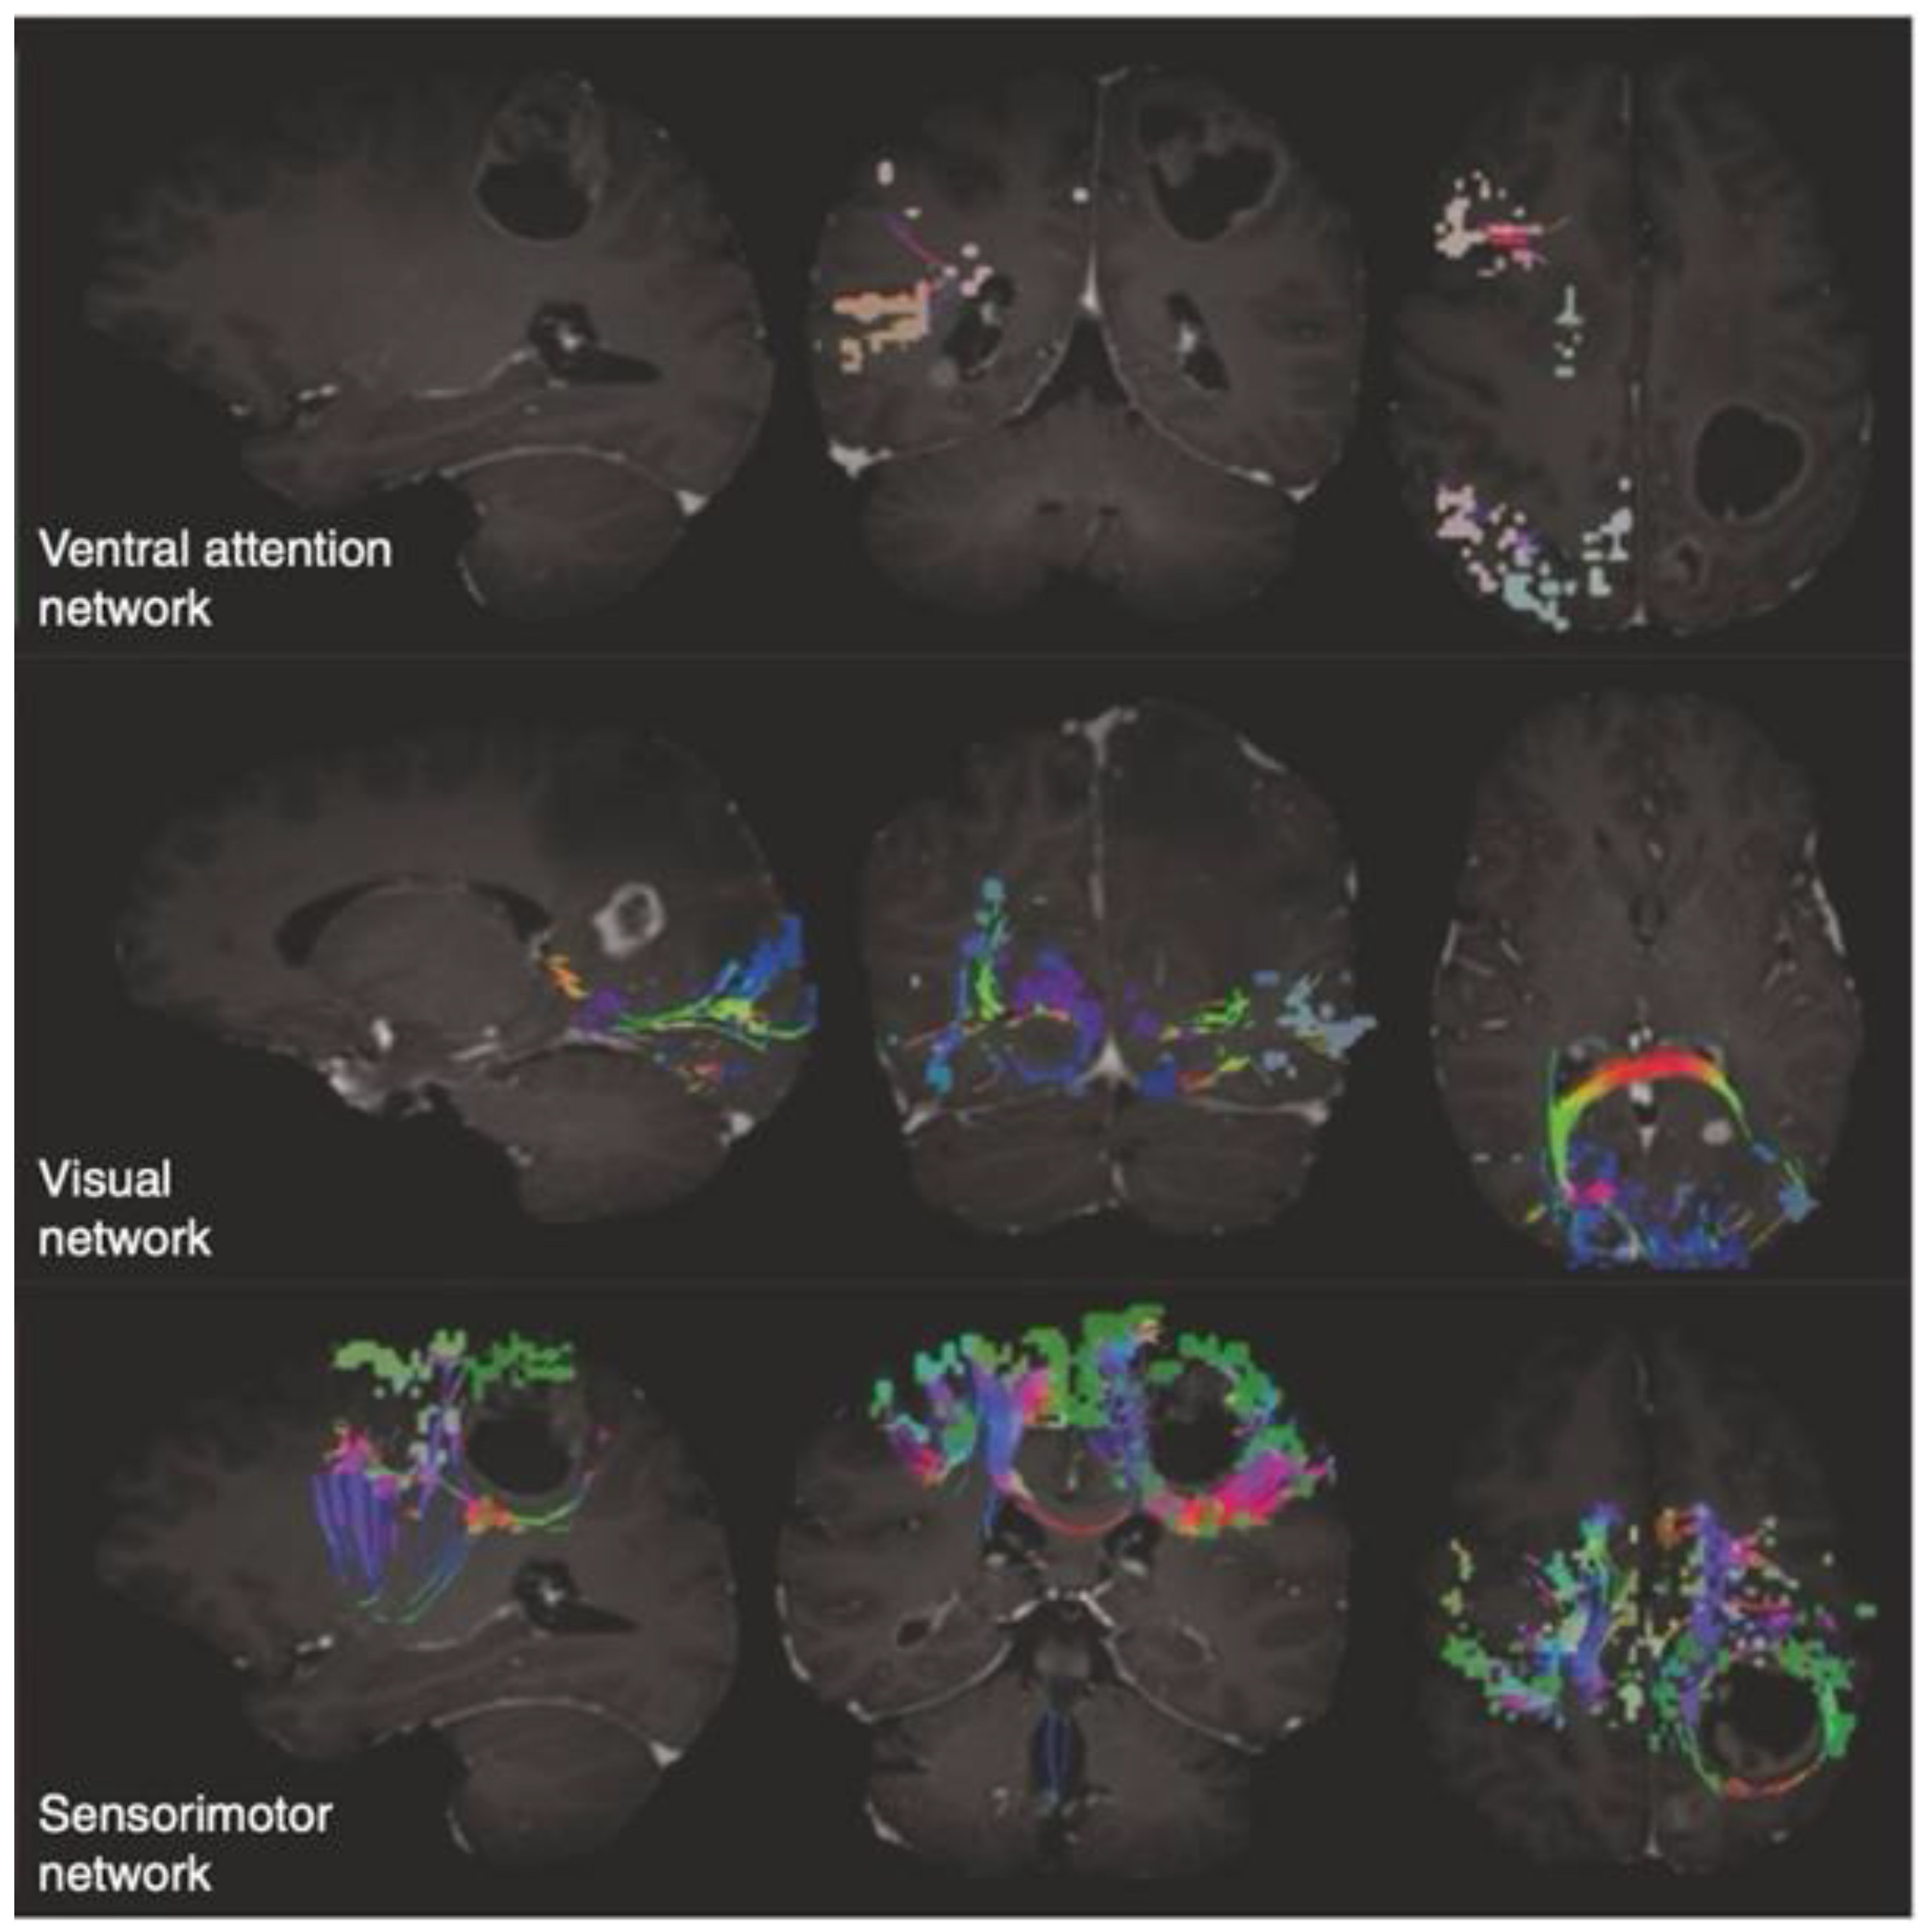

3.2. An Insight into the Application of QuicktomeTM for the Identification of Brain Networks in Patients Affected by Primary Intra-Axial Neoplasms

- Wu, Z.; Hu, G.; Cao, B.; Liu, X.; Zhang, Z.; Dadario, N.B.; Shi, Q.; Fan, X.; Tang, Y.; Cheng, Z.; et al. Non-Traditional Cognitive Brain Network Involvement in Insulo-Sylvian Gliomas: A Case Series Study and Clinical Experience Using Quicktome. Chin. Neurosurg. J. 2023, 9, 16. [Google Scholar] [CrossRef]

- Yeung, J.T.; Taylor, H.M.; Nicholas, P.J.; Young, I.M.; Jiang, I.; Doyen, S.; Sughrue, M.E.; Teo, C. Using Quicktome for Intracerebral Surgery: Early Retrospective Study and Proof of Concept. World Neurosurg. 2021, 154, e734–e742. [Google Scholar] [CrossRef] [PubMed]

- Morell, A.A.; Eichberg, D.G.; Shah, A.H.; Luther, E.; Lu, V.M.; Kader, M.; Higgins, D.M.O.; Merenzon, M.; Patel, N.V.; Komotar, R.J.; et al. Using Machine Learning to Evaluate Large-Scale Brain Networks in Patients with Brain Tumors: Traditional and Non-Traditional Eloquent Areas. Neuro-Oncol. Adv. 2022, 4, vdac142. [Google Scholar] [CrossRef] [PubMed]